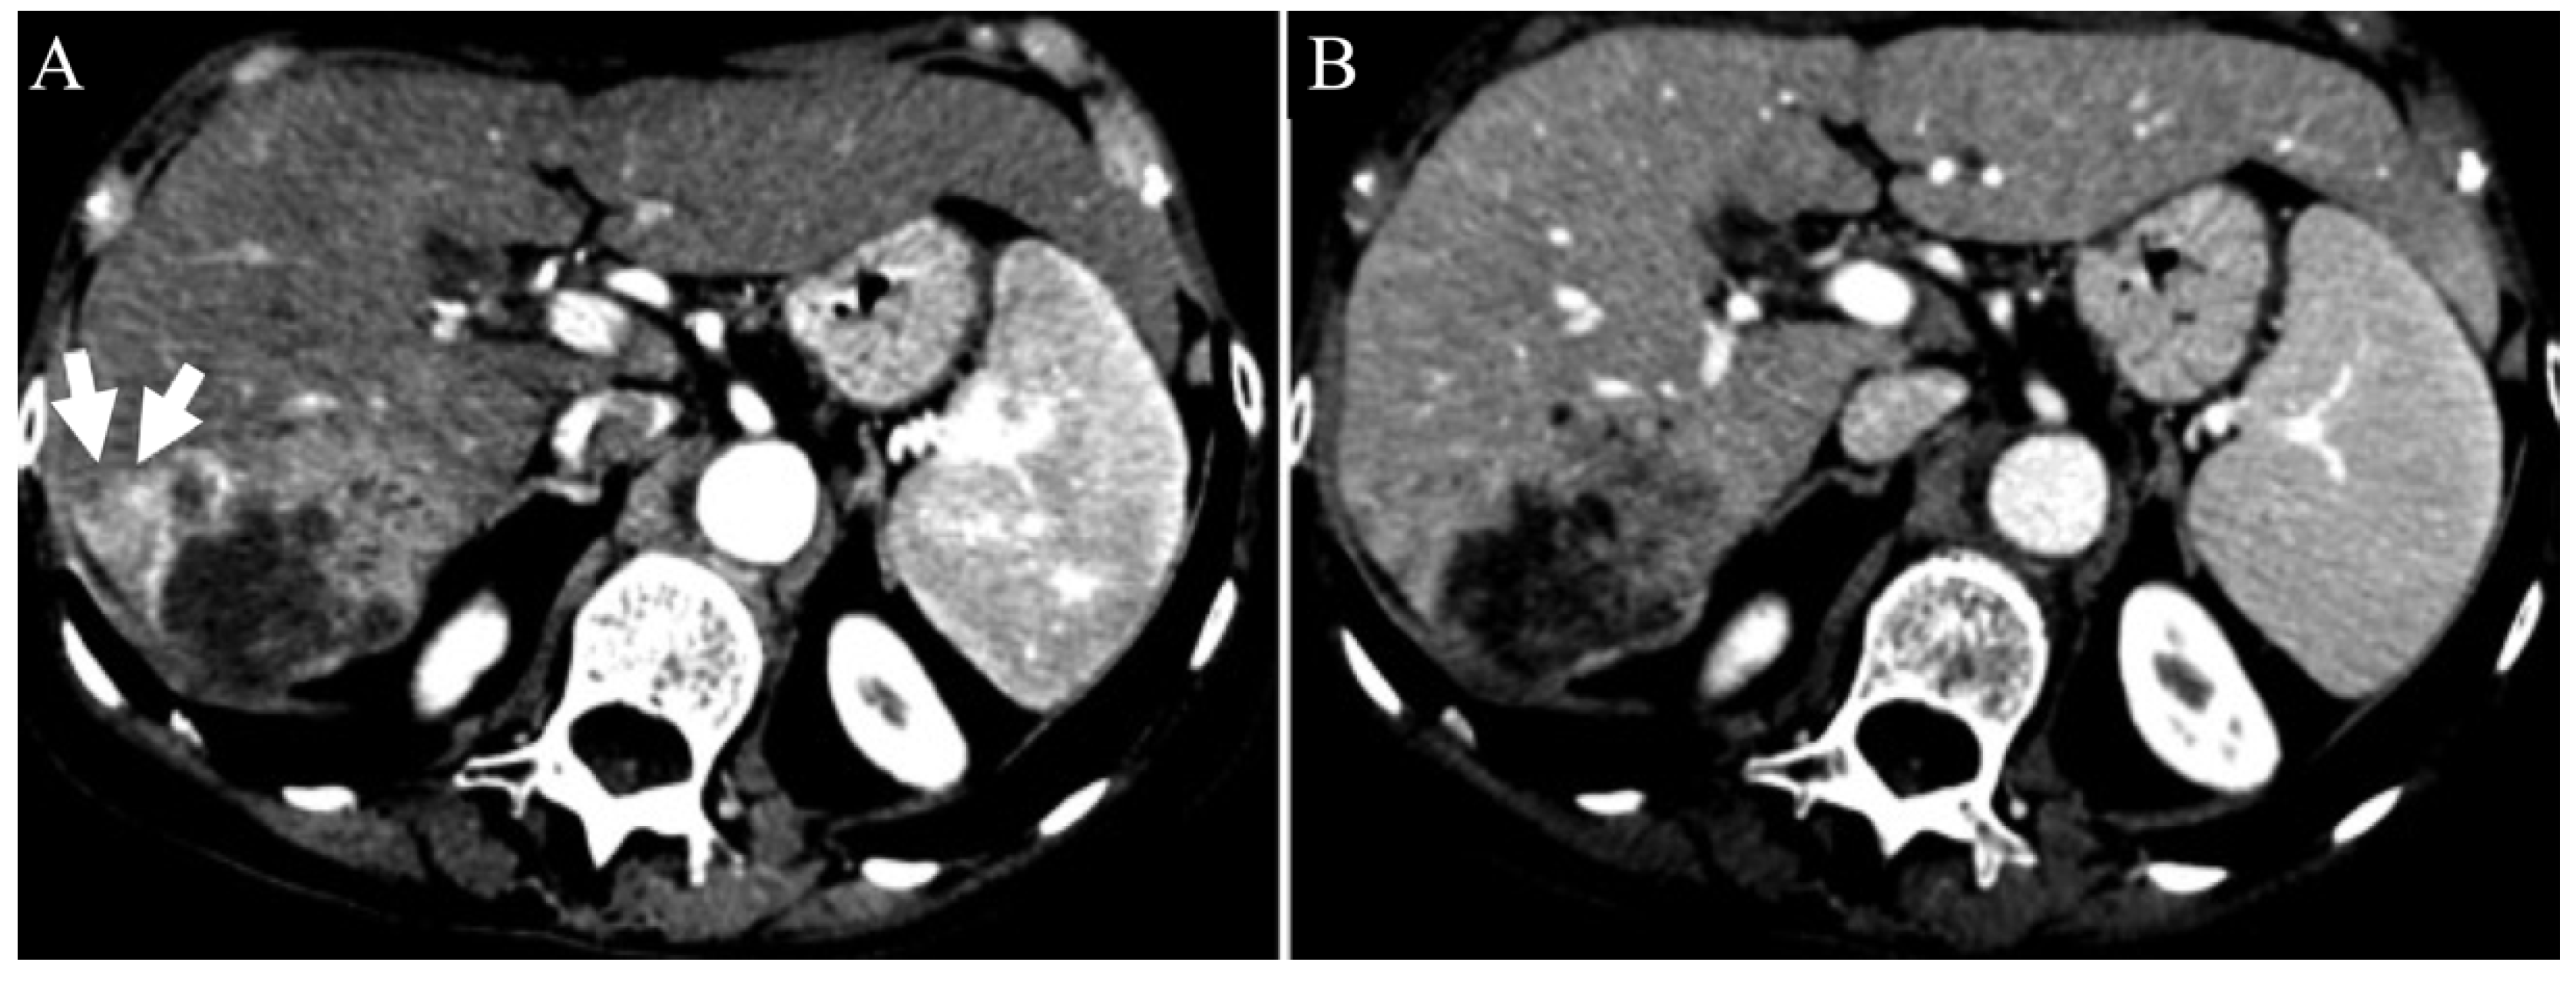

| Irregular margins | 21 (58.3%) | 26 (47.3%) | 0.391 |

| Peritumoral enhancement | 4 (11.1%) | 6 (10.9%) | 1.000 |

| Diameter > 50 mm | 21.300 (4.200–107.700) | <0.001 | 21.300 (4.200–107.700) | <0.001 |